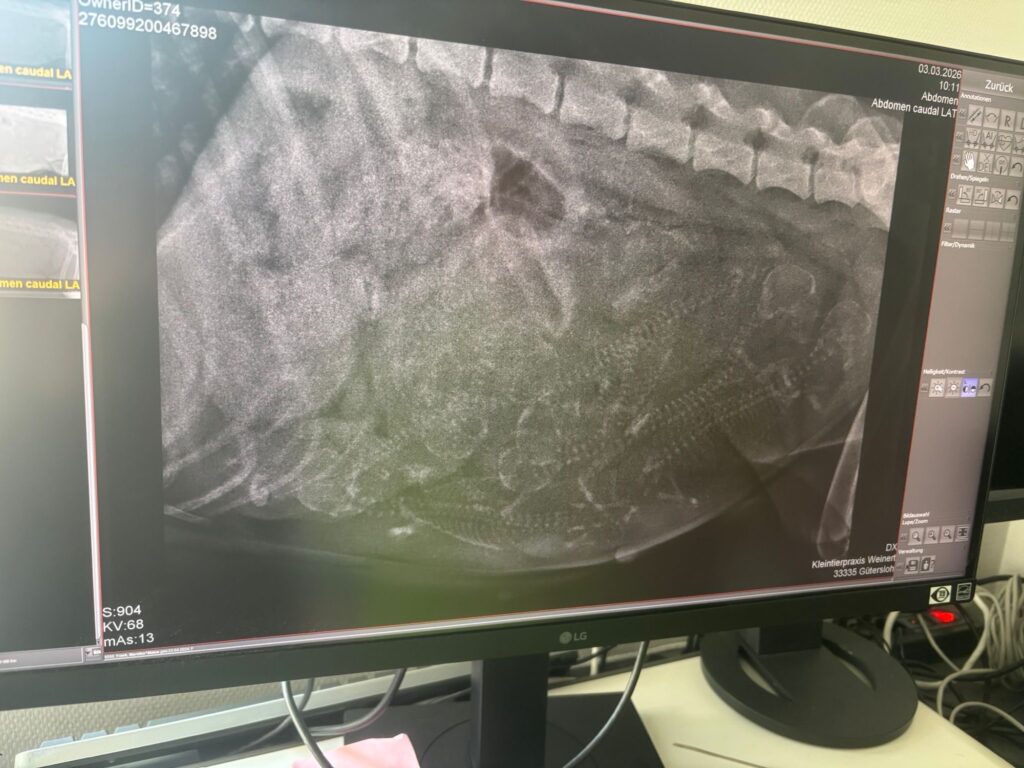

- Malou’s HundetagebuchHeute waren wir beim Tierarzt 🐕 ist ziemlich unheimlich da 👀